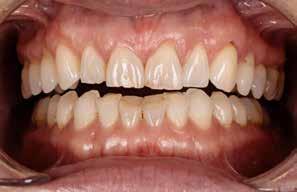

Patienttilfælde 1 (Fig. 1) er en 37-årig kvinde, henvist efter succesfuld behandling af stadie 3-parodontitis. Der er nu sundt

Før behandling

parodontium, ingen pocher over 4 mm, og både blødnings- og plakindeks er under 10 %. Patienten er motiveret for ortodontisk behandling, da hendes tænder er vandret over tid, delvist som følge af reduceret parodontium.

Der ses anterior trangstilling i begge kæber og overerupterede 1+1 og 2,1-1,2, hvilket resulterer i dybt bid med 2- tæt på ganepåbidning. Der er normale sidetandsrelationer, men der ses 5 mm horisontalt overbid (HOB) og 7 mm vertikalt

overbid (VOB). Papillen mellem 1+1 er betydeligt reduceret pga. fæstetab, og de mesialt kippede 1+1 har resulteret i en ”dark triangle”. Den facioorale funktion er for nuværende i.a. Panoramarøntgen (Fig. 1, I) viser marginalt knogletab i begge kæber og fravær af 8,7+7,8 og 8,7-8.

Objektivt anbefales behandling af det dybe bid, som ubehandlet forventes at forværres yderligere over tid. Patienten har ønske om behandling med æstetisk ortodontisk apparatur, alignere, og det vurderes muligt at behandle malokklusionen med alignere. Dog anbefales det generelt, at alignere undgås eller benyttes med væsentlige modifikationer af alignerens retention ved tandmobilitet, da dette ellers kan medføre jiggling, når aligneren tages af og på mange gange dagligt. På den anden side er der nogen evidens for, at alignerbehandling er associeret med bedre renhold og parodontal sundhed sammenlignet med fast apparatur (16).